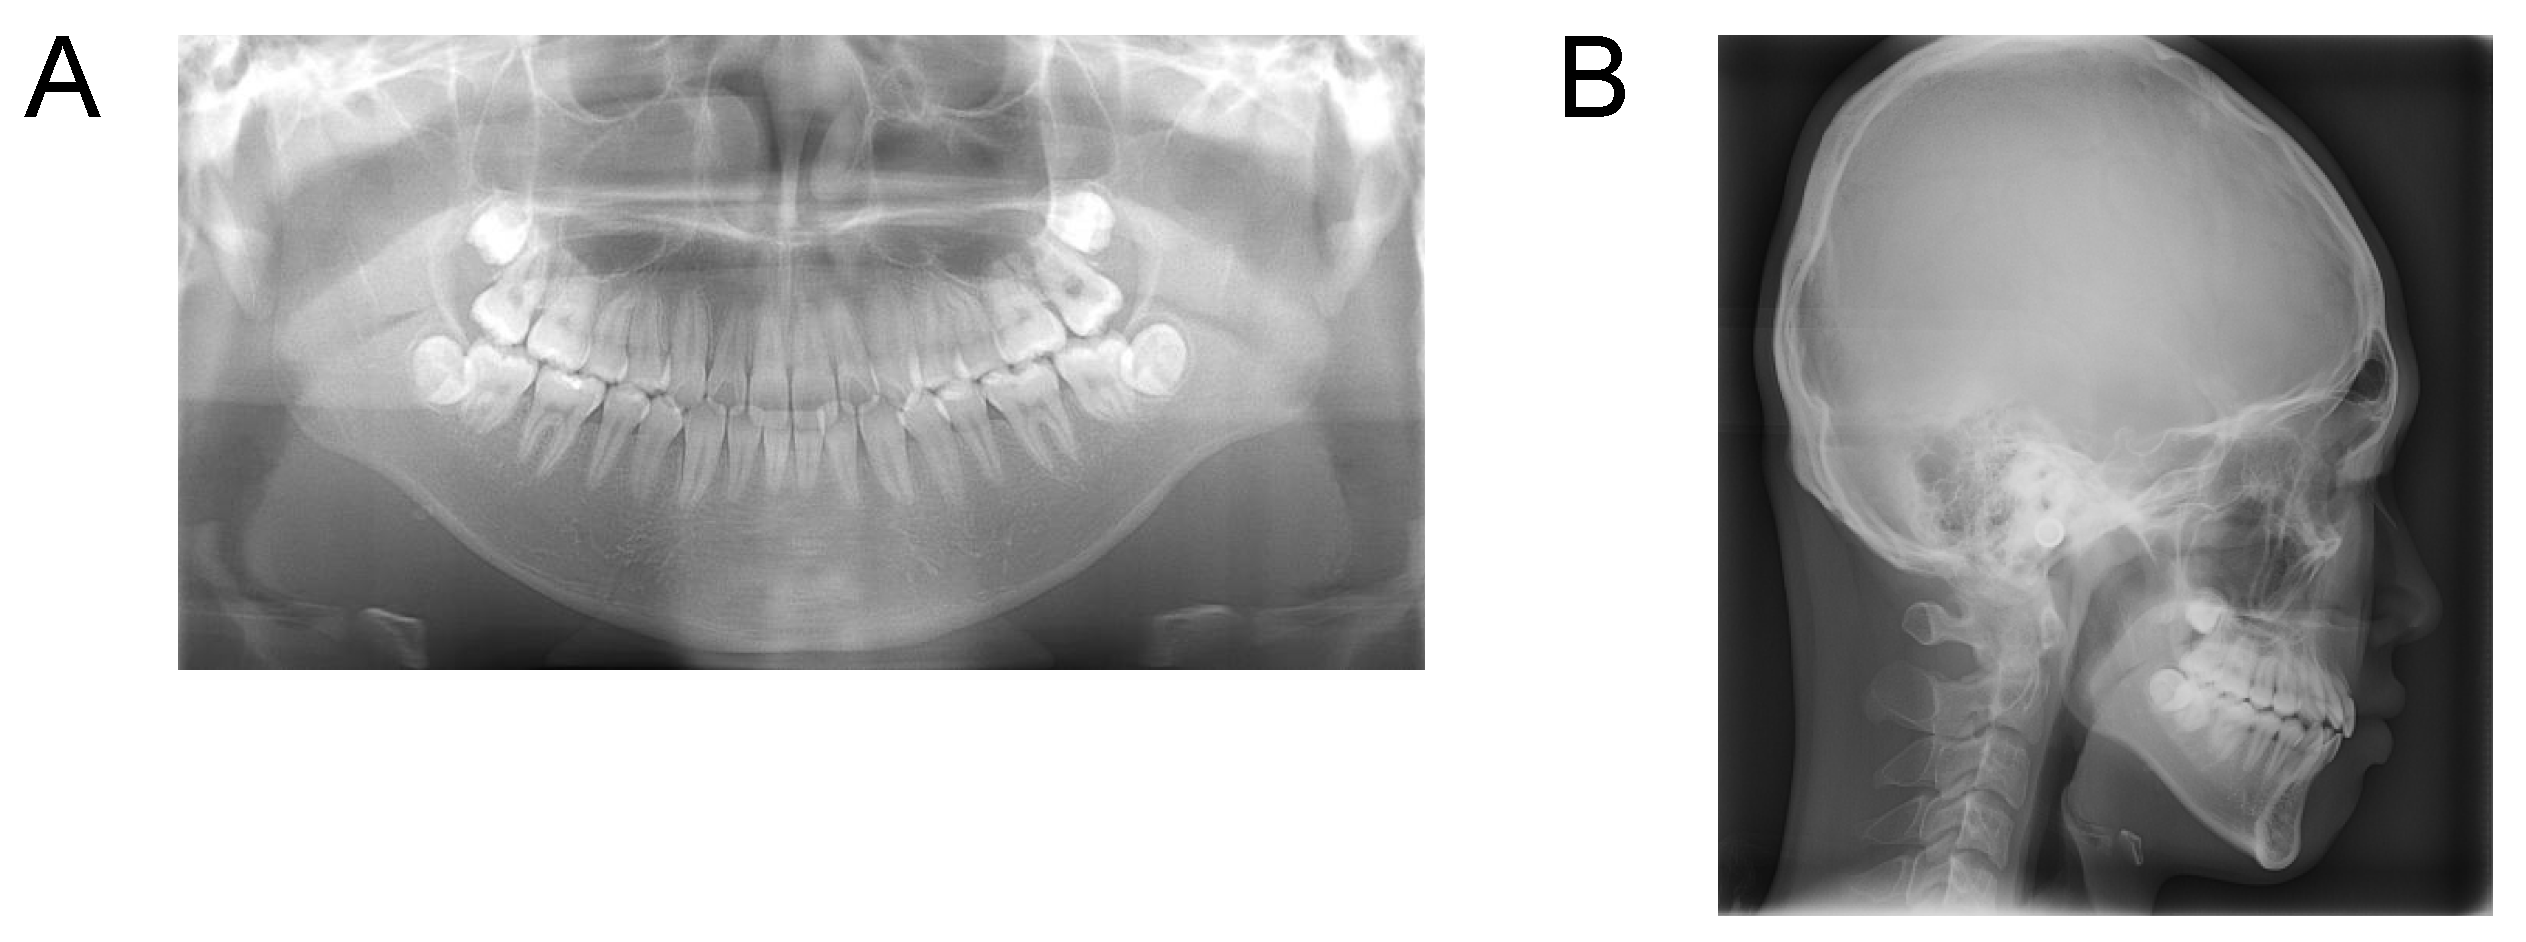

Case 1. Findings from initial examination